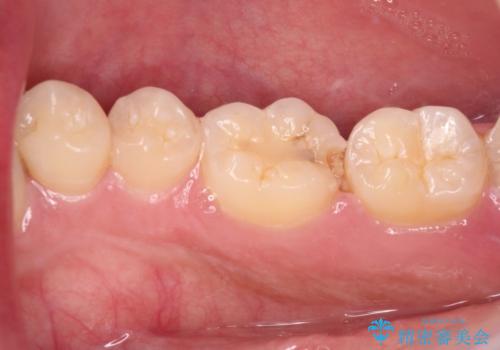

- 右下の奥歯が噛んだ時に痛み、冷たいものがしみることを主訴として来院された患者様です。

精査の結果、歯が欠けていてその下に虫歯が認められました。

また、咬合面(歯の噛む面)に以前治療した樹脂の詰め物があるため、一度外して虫歯を完全に除去し、

精度の高いセラミックインレーにて修復処置することとしました。